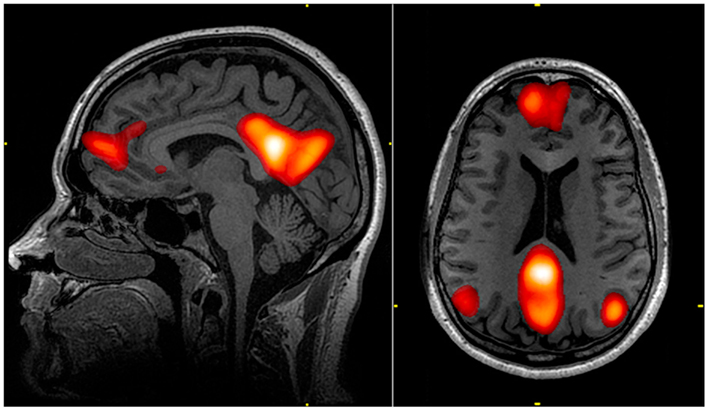

などが知られています(Fig.2 Buckner et al., 2008より引用)。Fig.2のA〜Dが、上述の実験状況で観測された脳活動です。

Fig.2 色々な状況でのDMNの活動。 A. 自分に関する記憶、B. 未来の想像、C. 心の理論、D. 道徳的意思決定を行っているときの脳活動パターン。Buckner et al., 2008より引用。